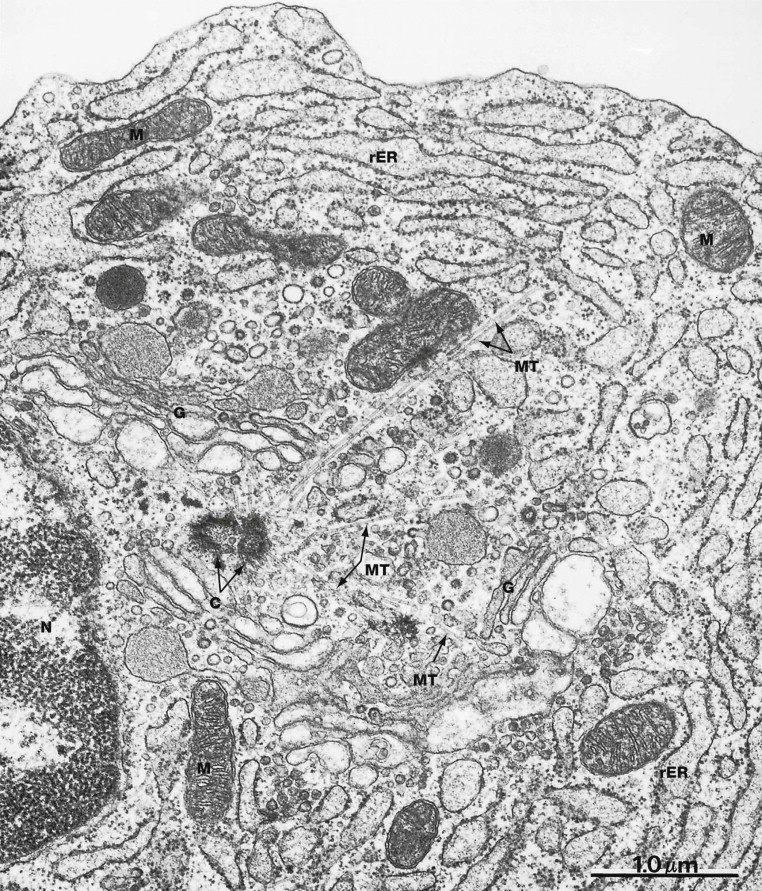

What is this cell?

plasma cell